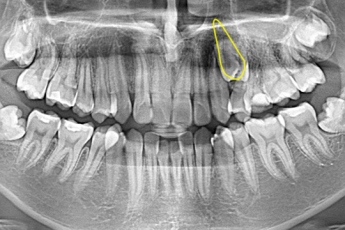

- 매복치교정

BEFORE & AFTER